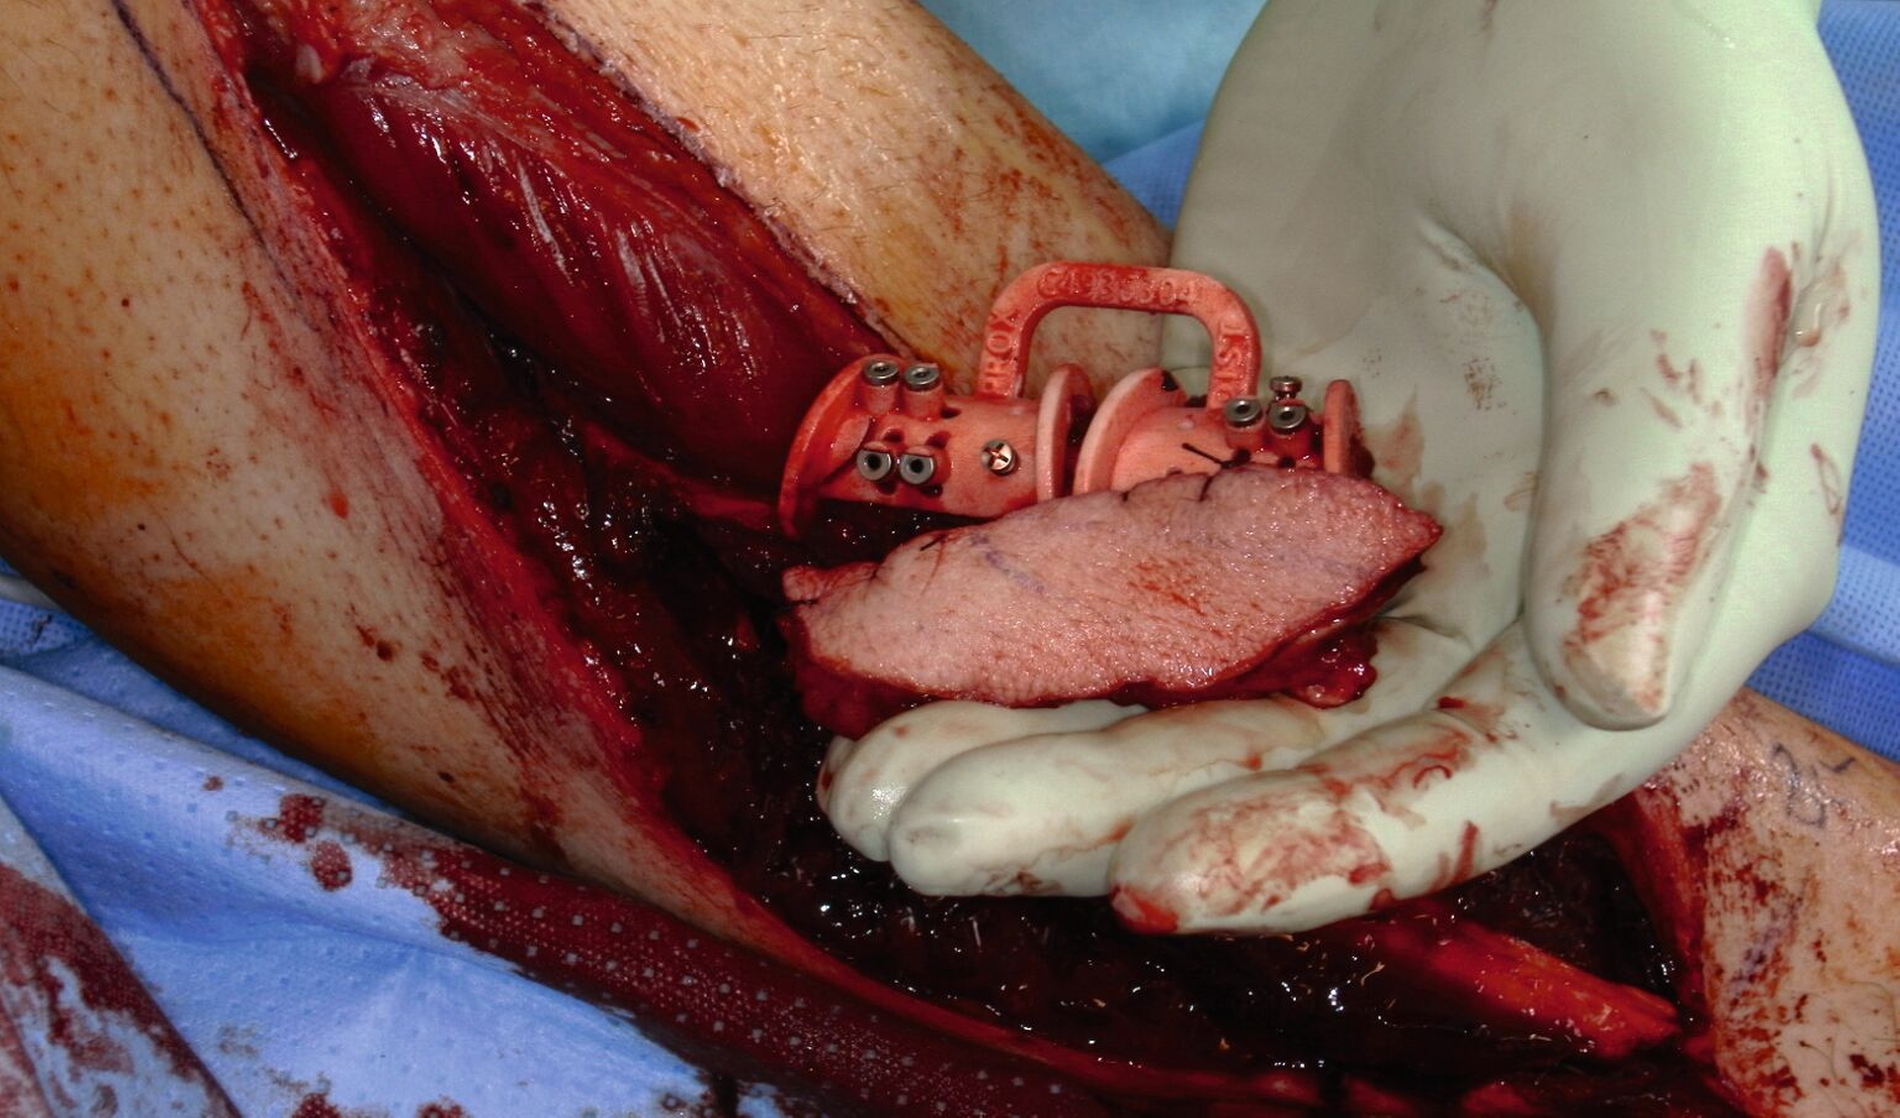

In Intubationsnarkose wurde die Kontinuitätsresektion von extraoral mittels CAD/CAM-gefertigten Schnittschablonen durchgeführt (Abbildung 5). Das entnommene Fibulatransplantat (Abbildung 6) wurde osteotomiert und mittels individuellen Osteosyntheseplatten zur Überbrückung des Defekts fixiert (Abbildung 7). Die notwendigen Gefäßanastomosen erfolgten End-zu-End an der Arteria thyroidea superior und End-zu-Seit an der Vena jugularis interna.